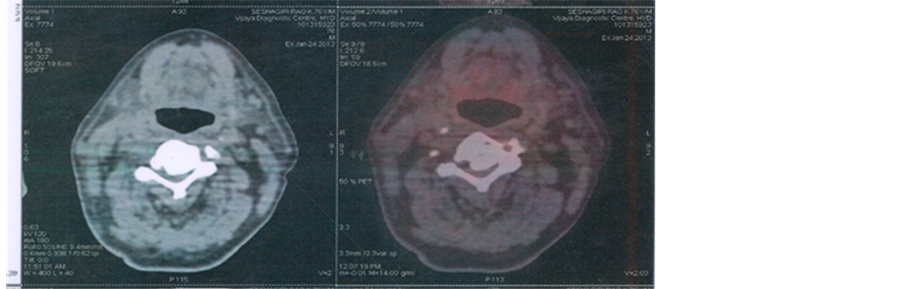

2.6. Case 6

A 73-year-old male patient presented with proliferative growth measuring 4 cm × 3 cm involving the lateral and under surface of anterior 2/3rd tongue with extension on to the floor of mouth. Biopsy of the lesion was moderately differentiated squamous cell carcinoma of tongue. The patient had right submandibular node enlarged and measured 2.5 cm × 2 cm. Patient was planned for weekly carboplatin 150 mg in view of poor general condition and nimotuzumab 200 mg weekly for 6weeks. Patient received radiation dose of 6600 cGy/33 fractions for 6½ weeks by IMRT protocol. Patient had responded well to treatment (Figure 6).

Figure 6. (6a), (6b) and (6c): 2nd week, 3rd week and 4th week of treatment respectively showing tumour regression.